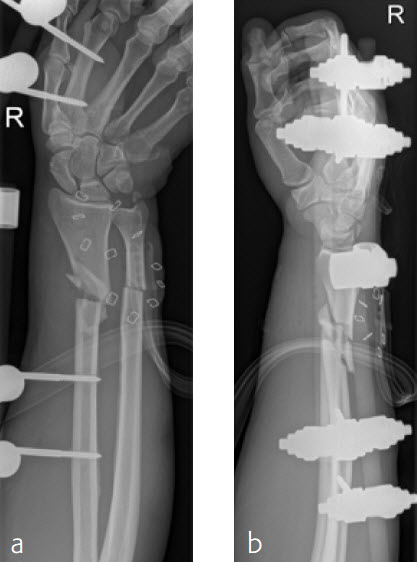

A 59-year-old farmer suffered a crush injury with an open forearm fracture (AO22 C2, Gustilo and Anderson IIIB) (Fig 1). Initial stabilization was carried out by external fixator (Fig 2). After four rounds of debridement and capillary ingrowth of a splitting skin graft at day 17, the VA LCP Extra Long Two-Column plate was used for fixation of the radius. A 2.7 mm LCP Condylar Plate was used for fixation of the ulna. The plates provided good stability for a functional after-treatment.

At the 3-month follow-up, the patient was full weight bearing with healing fractures (Fig 3).